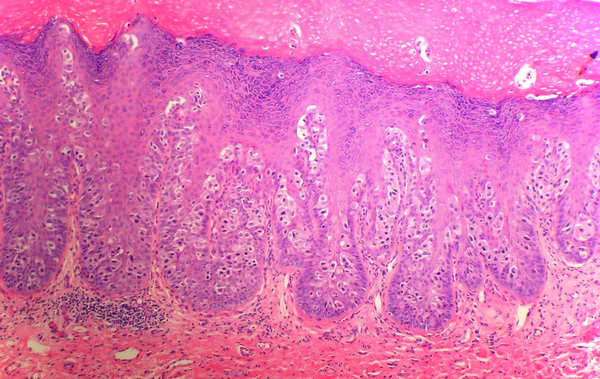

Главными методами диагностики являются цитологическое и морфологическое исследования[2]. В эпидермисе обнаруживаются клетки Педжета.